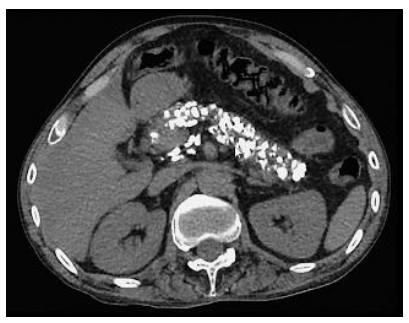

Homem,45 anos, etilista por 10 anos. Na investigação de uma dor abdominal, realizou a TC abaixo.

Qual sintoma NÃO é esperado nessa situação?

Imagem associada para resolução da questão